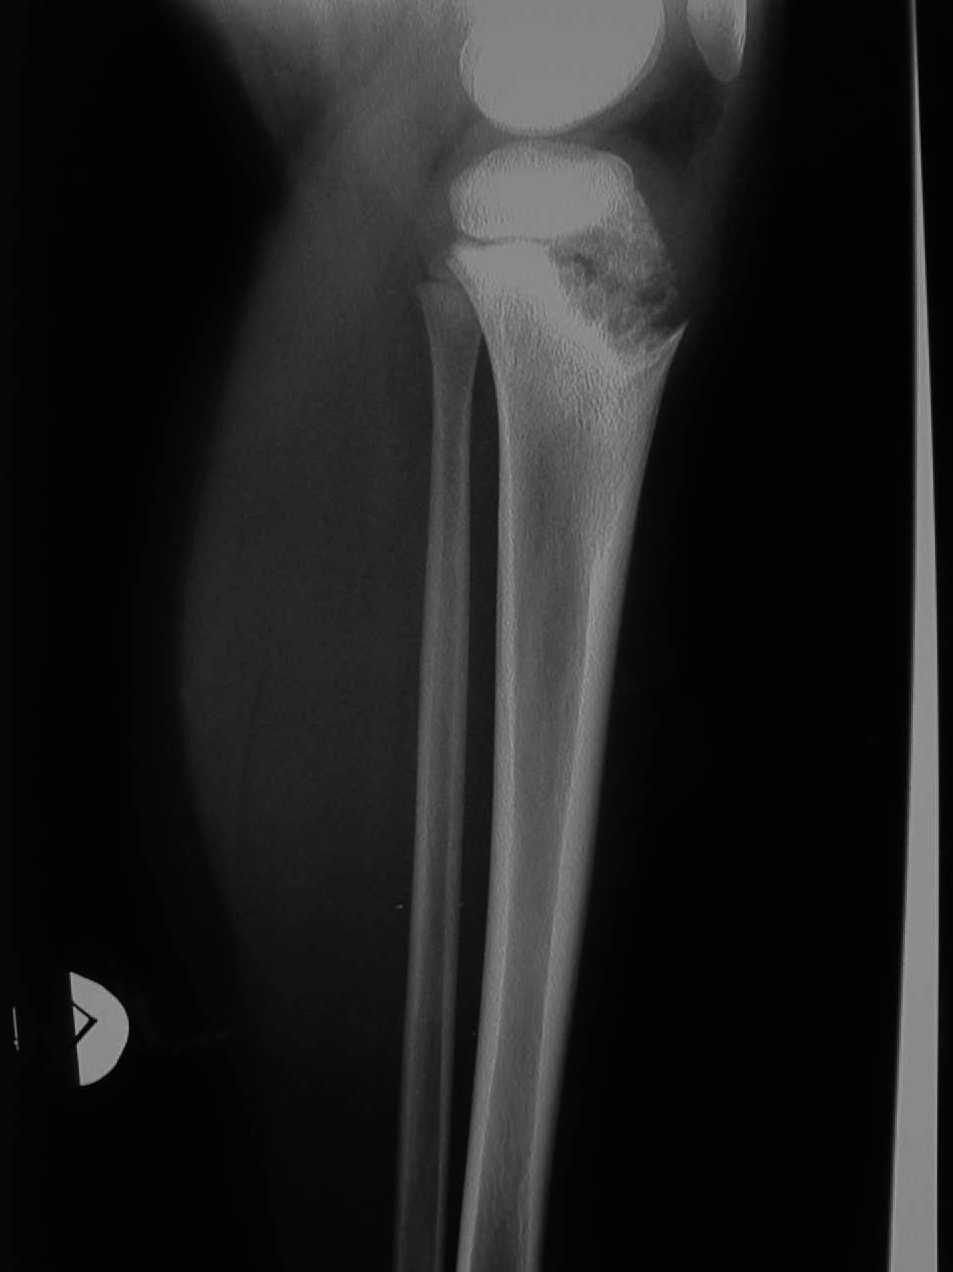

All'et� di 3 anni compare una tumefazione dell'epifisi prossimale della tibia dolente sia alla palpazione che dopo carico, con cute sovrastante calda. Inizialmente la sintomatologia dolorosa era ben controllata dall'uso dei FANS, ma successivamente per il persistente dolore � stato necessario iniziare un trattamento con gli steroidi a basso dosaggio (5 mg/die). Successive radiografie hanno mostrato un'estesa lesione litica con reazione periostale sclerotica nella metafisi dell'estremit� prossimale della tibia sinistra (Figura 2).

Nel 50% dei casi � presente una uveite cronica anteriore, ma non sono riportati in letteratura sinechie o glaucoma (8). Una sordit� progressiva di tipo neurosensoriale di grado variabile si pu� manifestare in epoche successive. Il coinvolgimento articolare � estremamente variabile, dalla semplice artralgia con tumefazione transitoria alla artropatia severa e simmetrica. Modificazioni epifisarie e metafisarie sono conseguenti ad una crescita cartilaginea in esubero (tipica l'eccessiva crescita della patella). In letteratura � descritta la possibilit� di degenerazione maligna (condrosarcoma) di lesioni osteo-cartilaginee (9). In rari casi una reazione periostale � stata osservata molto precocemente, mentre non � presente ispessimento sinoviale ma si pu� riscontrare versamento, probabilmente come conseguenza delle alterazioni epifisarie.